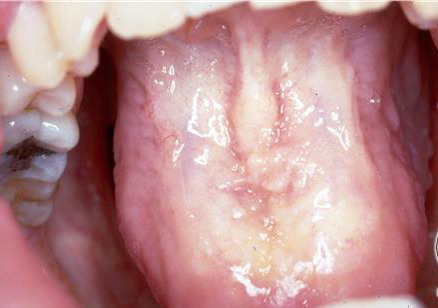

Hyalinosis Cutis et Mucosae=تنكس هياليني جلدي ومخاطي